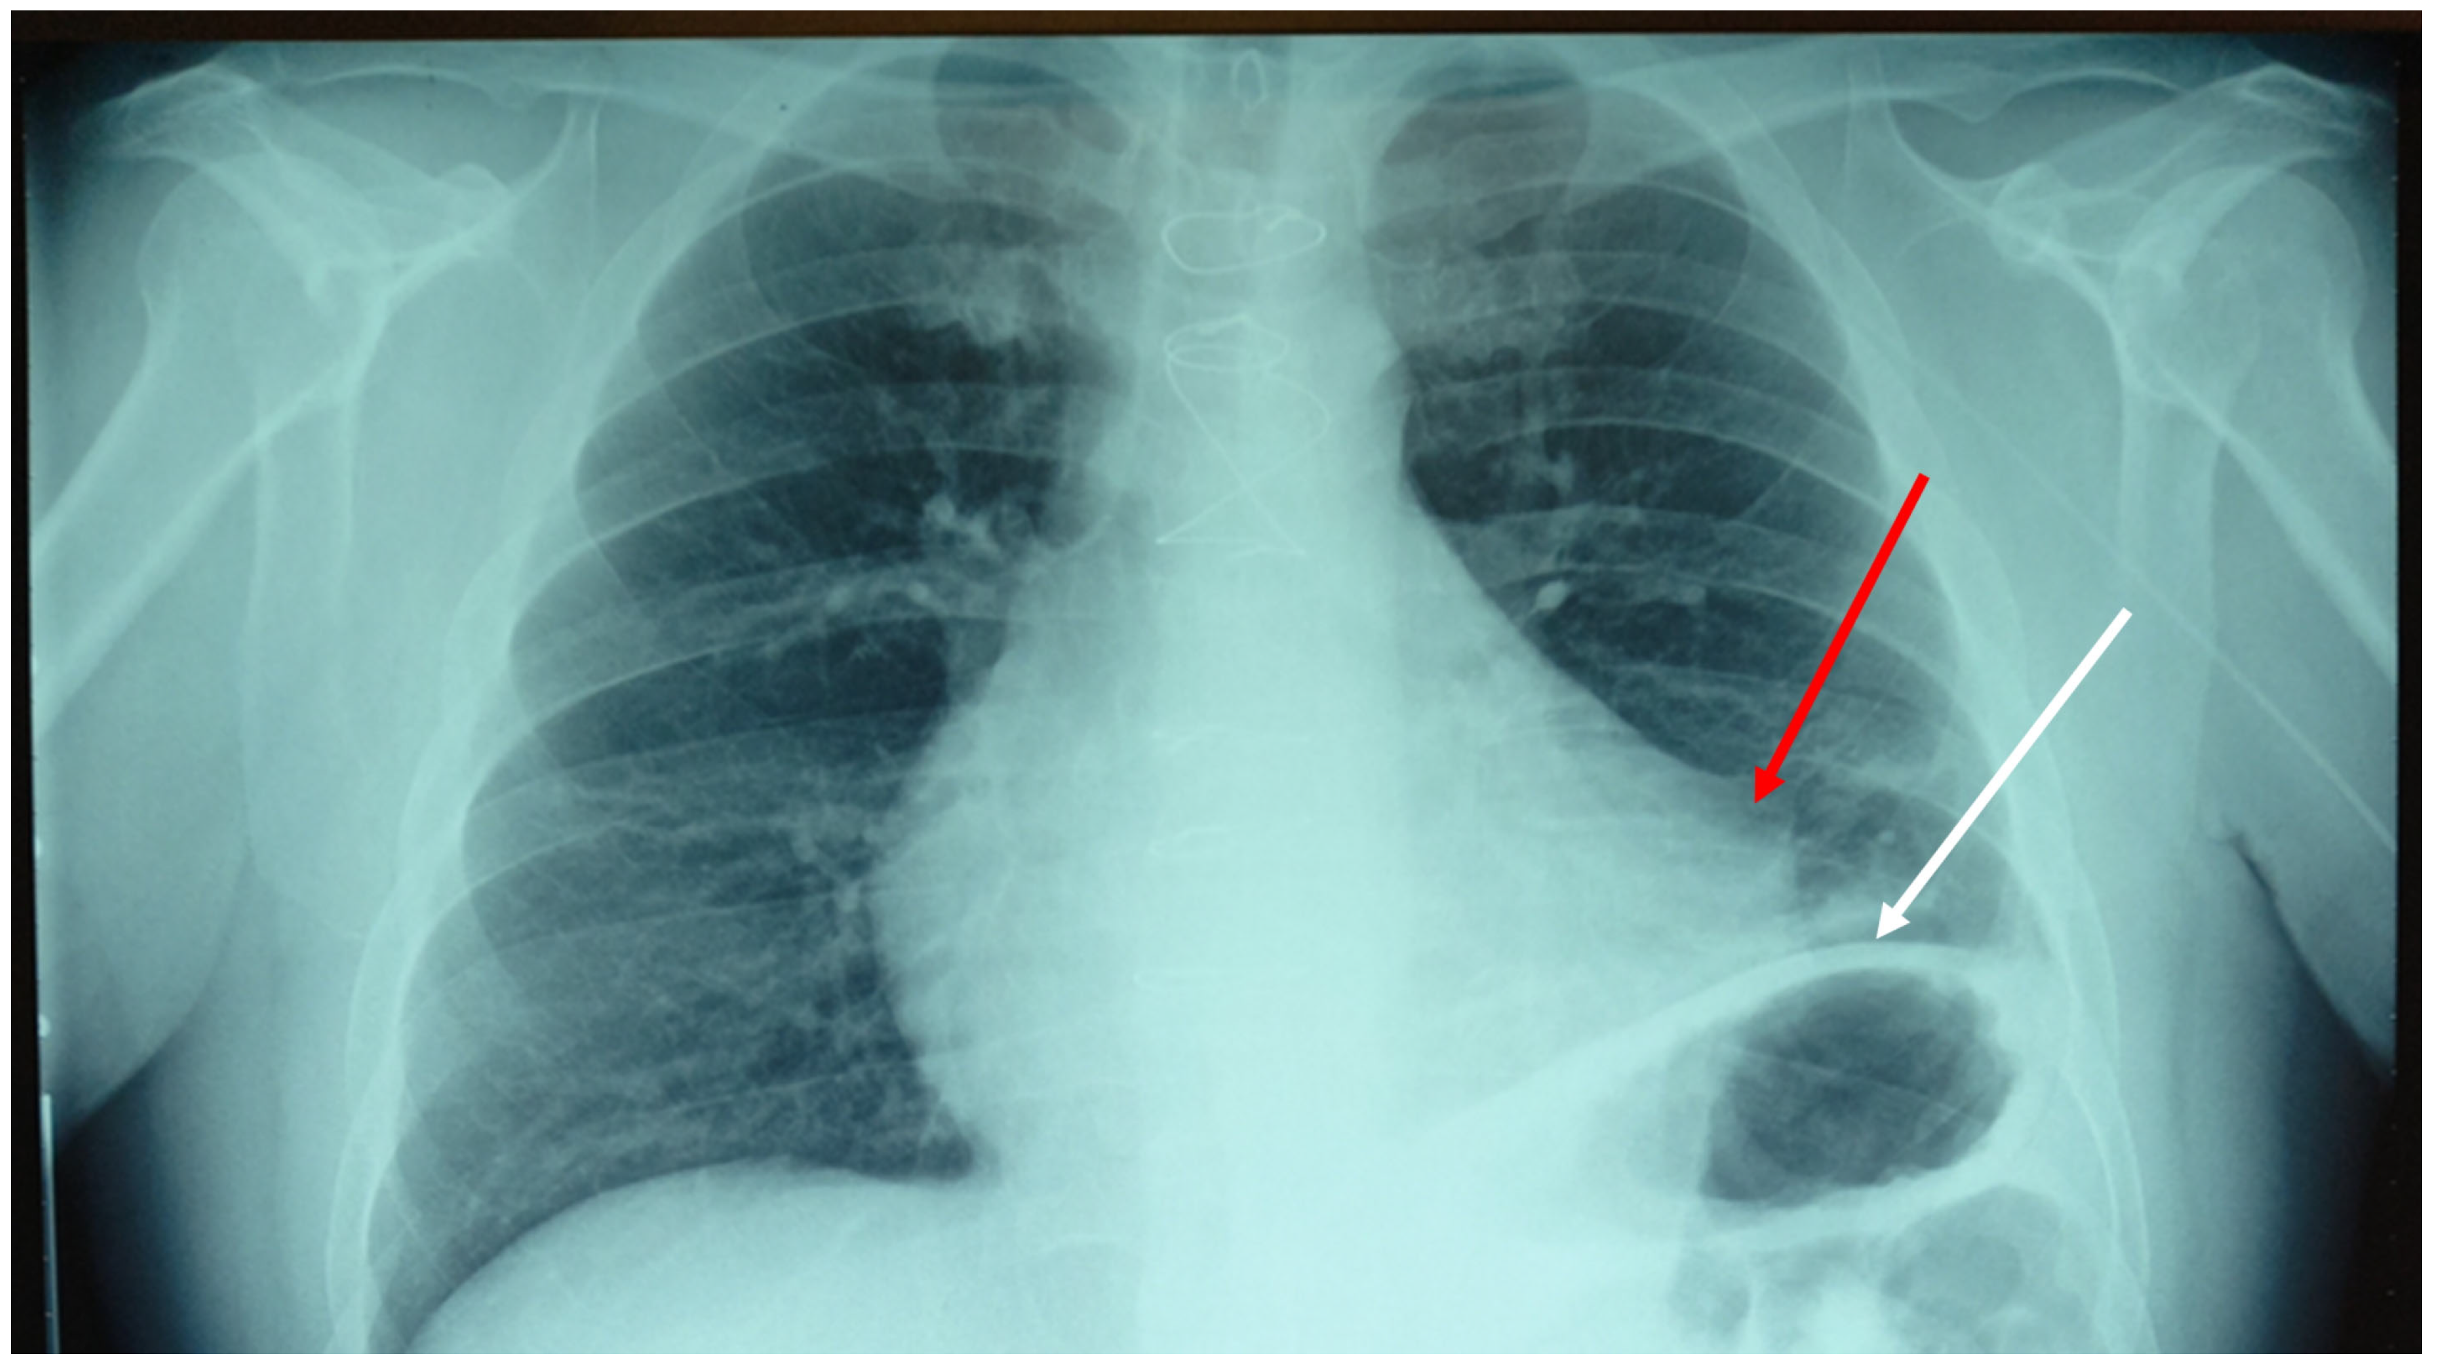

2. Case Presentation